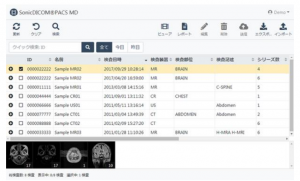

医用画像管理システム『SonicDICOM PACS MD』について、クラウド版を国内医療機関向けに 2020年12月より提供を開始する。

本製品は、CR や CT、MRI などの検査装置から発生するデジタルな医用画像データを保管、管理し、それらの画像を Web ブラウザで参照することができるソフトウェア。2018年の販売開始以来、Webブラウザベースの高速画像ビューアを搭載し、リーズナブルなコストで導入できることから、高い評価を得ている。

また、本製品は、従来のハードウェア一体型の医療機器ではなく、ソフトウェア単体(ダウンロード方式)で提供してきた。今回、医薬品医療機器等法に基づく変更手続きが完了し、ダウンロード方式に加えて、クラウドコンピューティングによる提供を開始する。これにより、院内の情報共有のみならず医療連携や遠隔診療に向けてさらに高度な利便性が期待できる。